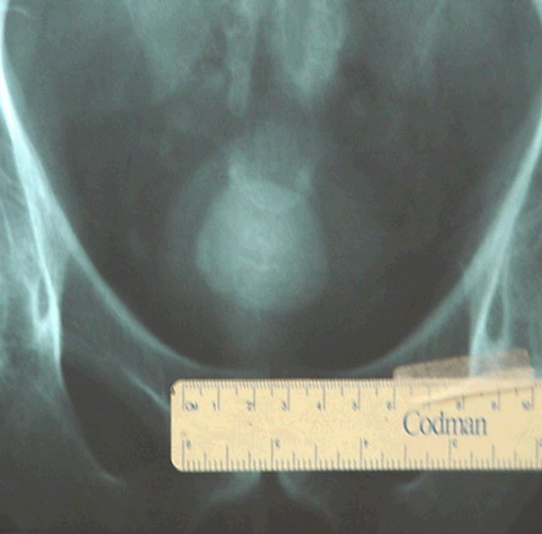

# CÁLCULOS URINÁRIOS

SÃO VERDADEIRAS PEDRAS FABRICADAS NORMALMENTO PELOS RÍNS MAS TAMBÉM PODEM SE ORIGINAR NA BEXIGA E DE TAMANHOS , FORMAS E COMPOSIÇÕES VARIADAS . INICIAM-SE COMO PEQUENOS CRISTAIS NA URINA QUE SE COALESCEM FORMANDO OS TEMIDOS E DOLOROSOS CÁLCULOS URINÁRIOS. TAMBÉM PODEM SER FORMADOS À PARTIR DE INFECÇÕES URINÁRIAS RECORRENTES OU CRÔNICAS